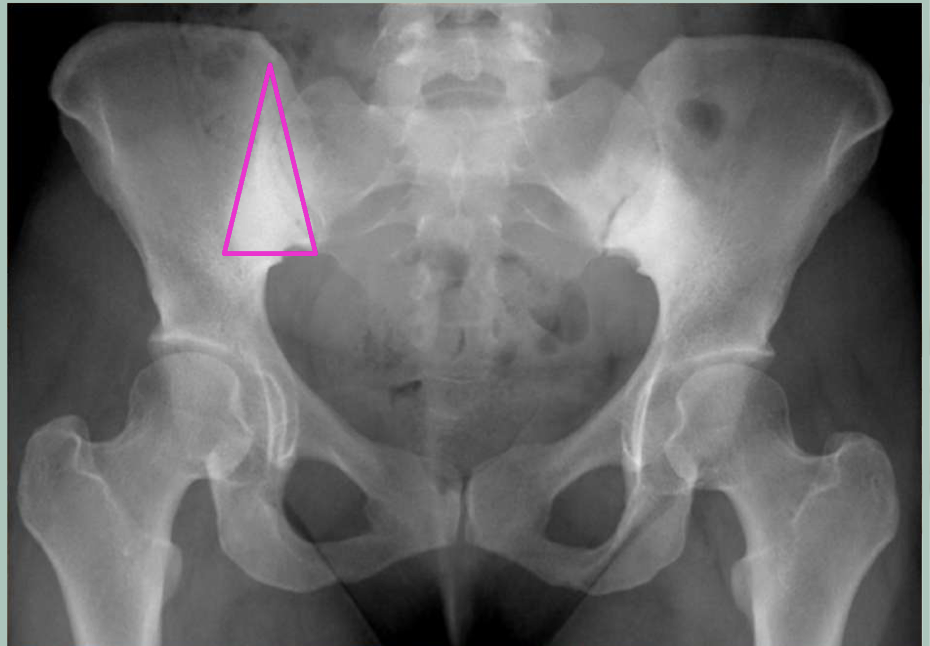

Osteitis Condensans Ilii (OCI)

sclerosis at inferior SI joint (Iliac side of joint ONLY)

NO erosions

triangular shape

What population is OCI most common in

postpartum females

(joint laxity, add sclerosis to increase stability)

Why is this image’s dx NOT Osteitis Condensans Ilii (OCI)

b/c erosions